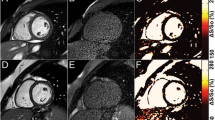

Figure 5a and 6 show real-time images obtained with the proposed pSAT sequence in patients with CHD. Figure 5b-e shows qualitative results obtained in the first patient. A pSAT angle range of 10°-30° resulted in balloon/blood contrast score > 2, quality of cardiovascular structure visualization score > 2 and image suitability for MR-guidance in 100% of cases. The ideal pSAT angle ranged from 20 to 30°. In the first patient, the catheter was easily guided from the IVC to the right atrium, right ventricle, main pulmonary artery and pulmonary branches; in the second patient, the balloon was guided from the IVC into the pulmonary arteries without difficulty (see Fig. 6 and Additional file 1: Video S1). The balloon and the cardiovascular structures were well visualized throughout each procedure. The first procedure was performed solely under CMR guidance. Support with x-ray was needed for the second patient (post-Fontan completion) to access the intracardiac anatomy across the fenestration from the lateral tunnel of the Fontan pathway using a wire.

Real-time images acquired in two patients during CMR-guided catheterization using the pSAT sequence with a pSAT angle of 30° (patient #1, a-c) and 40° (patient #2, d-f). Note balloon of the wedge catheter (see white arrow) at the inferior vena cava (a), main pulmonary artery (b) and left pulmonary wedge (c) in patient 1; and in the IVC (d) and LPA (e, f) in patient #2. Simultaneous visualization of catheter balloon and blood/heart structures was achieved with enhanced contrast and SNR using the proposed sequence